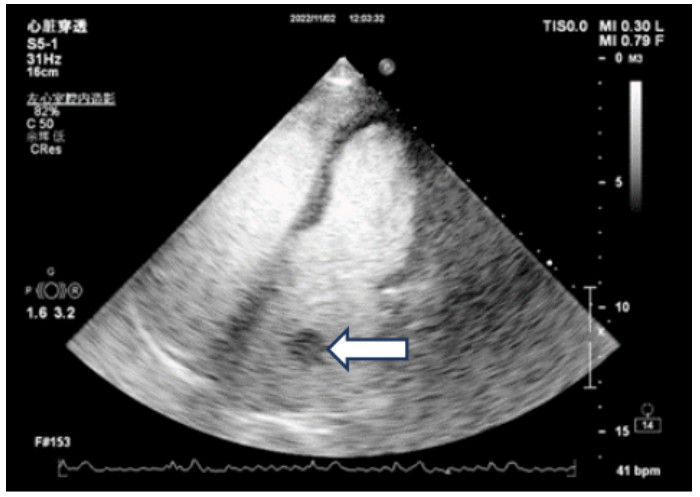

既往史:有高血压病史10年余,规律降压治疗,未监测血压。房颤病史2年余,2022年11月在本院超声心动图显示左心房见一不均质低回声团,位置随心动周期漂动(17 mm×16 mm)”(见图 1),左房前后径40 mm,左右径46 mm,上下径70 mm。LVEDD 39 mm,LVEF:60%。二尖瓣E峰0.92 m/s,最大压差3.39 mmHg(1 mmHg=0.133 kPa)。反流面积3.8 cm2,二尖瓣口频谱呈单峰。舒张期二尖瓣口前向血流,E < A,无舒张功能不全。进一步行经心脏超声造影提示:Flash后,左心室心腔内团块未见明显灌注(见图 2)。

| 注:左房内可见团块样回声影(箭头处),约17 mm × 16 mm 图 1 患者经胸腔超声心动图 |